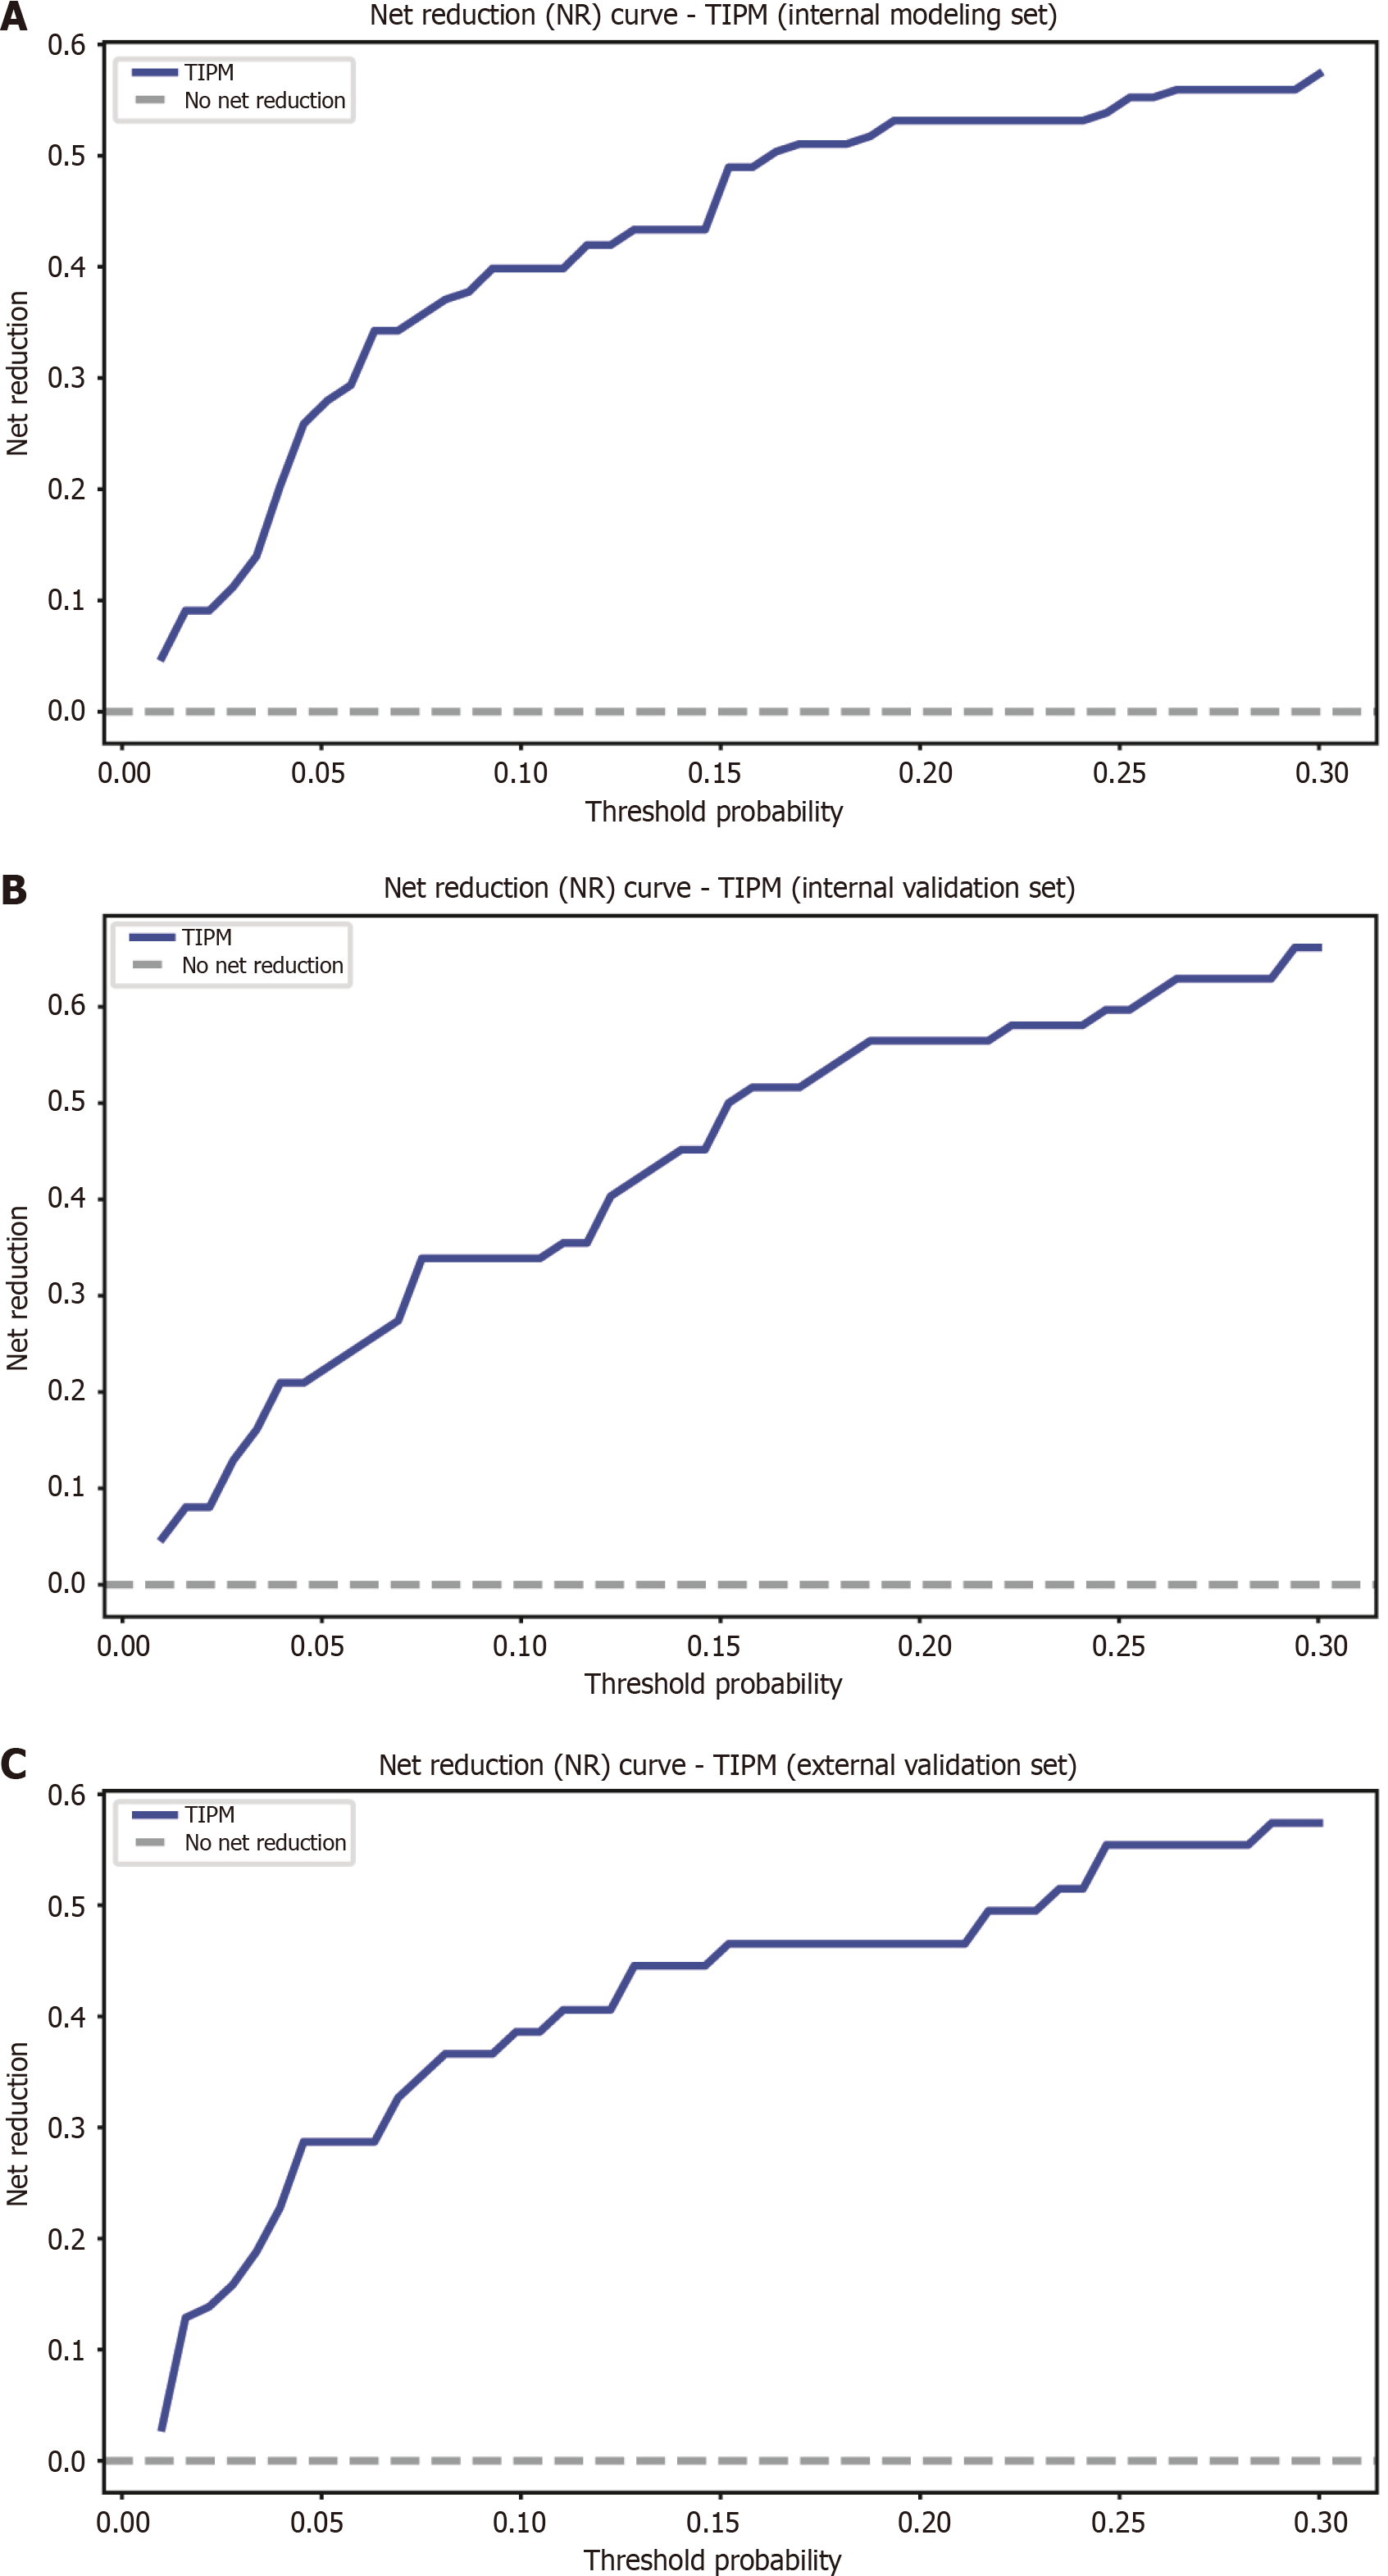

Figure 7 Net reduction graphs for Target Immunotherapy Predictive Model across various groups.

A: Net reduction (NR) curve for the Target Immunotherapy Predictive Model (TIPM) in the internal training cohort; B: NR curve for TIPM in the internal validation cohort; C: NR curve for TIPM in the external validation cohort. The graphs show that TIPM consistently achieves a greater net reduction, emphasizing its ability to minimize unnecessary interventions across all groups. TIPM: Target Immunotherapy Predictive Model.